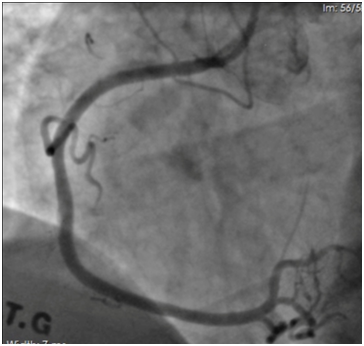

Coronary angiography revealed long, calcified > 40mm length lesion in right coronary artery proximal and middle part (Figure 1). Our decision was to treat this coronary lesion with BRS (Absorb BRS; Abbott Vascular, Santa Clara, CA, USA), following our centre plaque modification strategy, which is plaque modification before scaffold implantation using cutting or scoring balloon. In this case we used cutting balloon pre-dilatation 3.5x15mm 13 bars for each segment three times. Vessel dimensions were pre-analyzed with imaging methods to choose appropriate pre-dilatation balloon size. “PSP (Predilatation, Sizing, Post-dilatation) technique” that improves Absorb implantation is now widely described. Our centre following updated technique which is “IPSP (Imaging, Predilatation, Sizing, Postdilatation” technique. After plaque modification three BRS were implanted with total length 68mm. All scaffolds were implanted with small overlap to avoid uncovered gap which can provoke flow disturbances and possible future problems. Scaffold diameter was 3.5mm. An optimal scaffold apposition to vessel wall was achieved with non-compliant balloon 4.0x20mm. Post-dilatation was done with 15 bars in each segment. Mandatory for this intervention are imaging methods – intravascular ultrasound (IVUS) and optical coherence tomography (OCT). IVUS was performed before PCI, after plaque modification and after BRS implantation (Figure 2). OCT was performed after BRS implantation (Figure 3). Final angiography showed good result of procedure (Figure 4). Patient discharged next day on dual anti-platelet therapy for two years. Now patient reached six-month clinical follow-up with no cardiovascular events or bleeding.

Figure 1 Right coronary artery proximal and middle part long, calcified lesion > 40 mm of length.